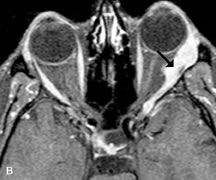

PATIENT PREPARATION Before MRI is performed, patients must be screened and prepared to avoid the potential hazards associated with the strong magnetic field. Patients who have ferrous aneurysm clips or cardiac pacemakers, who depend on life-support equipment, or who retain a possible metallic intraocular foreign body are not candidates for this imaging modality. MRI cannot be performed on obese patients who cannot fit into the bore of the magnet. Patients who are claustrophobic may not tolerate a prolonged period of study within the confines of the magnet, whereas others might do well if given a mild sedative. All worn metallic objects (e.g., necklaces, watches) should be taken off, credit cards set aside, and eye makeup removed before entering the room containing the magnet.5,20,34,35,36 NORMAL ORBITAL ANATOMY T1-weighted images provide the best anatomic details of the orbit because they display superior contrast resolution between normal structures (see Fig. 8). The vitreous has a long T1, resulting in an intermediate signal similar to brain, whereas the crystalline lens and sclera appear dark because of a longer T1 and short T2. The extraocular muscles, like all skeletal muscles, demonstrate a moderately long T1 and short T2 and highly contrast with the intense signal of the surrounding orbital fat (adipose tissue has an extremely short T1). The lacrimal glands appear as mottled areas of reduced intensity of the signal from the orbital fat in the lacrimal fossa. The optic nerves are seen with the same signal intensity as brain white matter and are hypointense relative to the orbital fat because their Tl is longer than the Tl of fat but shorter than the Tl of water. Cortical bone is not well delineated because it contains little free water, yielding minimal signal in MRI, and thus appears dark on all pulse sequences. This feature explains why MR images of the orbital apex and intracanalicular portion of the optic nerves are superior to comparable CT scans. Partial volume averaging of the bones in these regions obscures soft tissue details on CT images, whereas MRI reveals the signals only from the soft tissue structures with no cortical bone input. Bone marrow, on the other hand, is seen as a relatively intense signal because of its high fat content (see Fig. 8).37,38 T2-weighted pulse sequences are not ideal for imaging normal anatomy; however, they are particularly useful in revealing pathologic conditions (see Fig. 9). T2-weighted studies are most easily recognized by a bright vitreous signal. ORBITAL DISEASES Vascular Lesions Cavernous hemangiomas appear as well-circumscribed, smooth, usually intraconal masses that are isointense to muscle on T1-weighted images and hyperintense on T2-weighted images (Fig. 12). Patchy early enhancement is typically followed by diffuse, more homogeneous enhancement.39 The internal architecture of the mass, including septation and internal vasculature, may often be appreciated with high-quality orbital imaging.40 Lymphangiomas consist of ectatic vascular channels within a connective tissue stoma with varying degrees of lymphoid cellularity. On MRI, these tumors are typically poorly circumscribed, multicompartmental, and heterogeneous, often showing cystic dilations with fluid levels (Fig. 13). The signal characteristics within lymphangiomas vary considerably, reflecting cystic and solid components and the varying paramagnetic characteristics of blood at different stages of degradation.40–42 Acute hemorrhage appears hypointense on both T1- and T2-weighted formats. Methemoglobin present in subacute hemorrhage (3 to 14 days) leads to hyperintense signal on both T1- and T2-weighted images.41 A small percentage of lymphangiomas appear radiologically indistinct from orbital cavernous hemangiomas.43 Orbital varices are venous malformations that expand with increased systemic venous pressure, such as with Valsalva maneuvers. Because rapid acquisition of images during a Valsalva maneuver is important in imaging such a lesion, conventional or spiral CT is currently the modality of choice.44 MRI is an excellent modality for demonstrating enlargement of the cavernous sinus and dilation of the superior ophthalmic vein in patients with high-flow carotid-cavernous fistulas (Fig. 14).37MRA may be helpful in the evaluation of the venous outflow pattern. The rapidly flowing blood in these vascular structures carries the excited protons out of the section before they can be imaged, resulting in their dark appearance.5 In low-flow dural arteriovenous malformations, MRA may help define the arterial feeding vessels.45 Neural Lesions MRI is more effective than CT in delineating the intracranial optic nerves, chiasm, and optic tracts and, for this reason, is the preferred imaging modality in the evaluation of optic nerve disorders. The spatial relationships and image contrast of the orbital tissues with intraorbital optic nerve tumors is comparable between the two imaging modalities. The normal nerve is isointense to brain and appears enlarged and kinked owing to infiltration of an optic nerve glioma on T1-weighted images. Gliomas appear hyperintense on T2-weighted images and may be heterogeneous owing to cystic areas within the tumor. Contrast enhancement is variable.46 Intraorbital and intracranial optic nerve sheath meningiomas are usually isointense to cortical gray matter on Tl-weighted images and remain isointense on proton density studies (Fig. 15). Gd-DTPA is useful in delineating the intracranial extension of optic nerve meningiomas.7,47 The hyperostosis of bone and calcification associated with meningiomas are not demonstrated as well on MRI studies as on CT scans.20,37 Gd-DTPA–enhanced MRI also appears promising in the study of the permeability of the blood–brain barrier in selected optic neuropathies.22,48 MRI may reveal an enlarged optic nerve and some degree of contrast enhancement in cases of optic neuritis.49 Muscle Disorders Extraocular muscle enlargement in patients with thyroid-associated orbitopathy is demonstrated equally well with CT and MRI studies. However, the superior tissue contrast on MR images reveals better details of the relationships of the optic nerve to the thickened muscles at the orbital apex (Fig. 16).50 In addition, MRI may be able to differentiate between muscles that are enlarged as a result of edema and active inflammation and those enlarged because of fibrosis by their T2 relaxation times.21 Quantitative MRI was not found to be accurate in predicting the success of low-dose orbital irradiation.51 However, a muscular index relating the diameters of the rectus muscles to the bony orbital dimensions was useful in predicting optic nerve compression.52 MRI is also effective in imaging orbital tumors of mesenchymal origin, such as rhabdomyosarcoma, particularly in the assessment of extension into the anterior and middle cranial fossae (Fig. 17).37 The lack of any pathognomonic radiologic features necessitates rapid orbital biopsy when rhabdomyosarcoma is suspected. Osseous Lesions In general, CT is the imaging modality of choice when details of quantity and quality of bone are needed; however, abnormalities of bones can be detected indirectly by MRI. Cortical bone appears black (signal void) on MR images because of its low proton density and free-water content. The absence or discontinuity of the signal void of the orbital walls may represent bony destruction or fracture. Hyperostosis associated with prostate metastases or meningioma is visualized as areas of black smudging.50,53 Diseases in which the bone is replaced by pathologic tissues with a high free-water content, such as fibrous dysplasia, are well demonstrated on MRI. An intermediate signal intensity on T1-weighted images and hypointense signal on T2-weighted images is representative of fibrous dysplasia. Enhancement on post–Gd-DTPA MR scans is seen and is more evident in areas that are less mineralized.54 Cystic Lesions Dermoid cysts appear as rounded, well-defined lesions typically contiguous with an orbital bony suture. The high-intensity signal on T1-weighted images is attributed to the sebaceous-produced lipid contents (Fig. 18).31,50 Mucoceles may demonstrate a hypointense or hyperintense signal on MR images, depending on the concentration of proteinaceous or inflammatory fluid components. The integrity of the bony walls of the expanded sinus cavities cannot be assessed on MR as well as by CT.37,50,55,56 A high-signal intensity on Tl- and T2-weighted images is characteristic of orbital chronic hematic cysts because of the blood-breakdown products within the cysts.57 Trauma Although soft tissue relationships are usually better demonstrated on MRI, the evaluation of craniofacial bony trauma is preferable with CT. For example, prolapse of orbital fat through a fracture site and hemorrhage of adjacent tissues are demonstrated in an MR image, but the actual fractured bone is not imaged. Three-dimensional MRI of the orbit in subacute trauma has been described,58 although its precise role is not currently established. MRI has been suggested to be superior to CT in detecting intraorbital wooden foreign bodies.59,60 In a series of penetrating orbital injuries with organic foreign bodies, however, MRI was able to identify the foreign body in only four of seven cases.61 With an in vitro model for wood foreign body, McGuckin and colleagues concluded that CT was the imaging modality of choice.62 A careful history and, in selected cases, plain films to rule out a metallic foreign body are crucial before MRI is considered in patients with periocular trauma. MRI is particularly helpful in the detection and characterization of subperiosteal hematomas of the orbit (Fig. 19). They are most commonly seen in the subperiosteal space of the superior orbit as well-defined masses following a traumatic injury. The signal intensity varies depending on the acute, subacute, or chronic nature of the hematoma, based on the stage of blood degradation. Fresh hemorrhages are hypointense on T1-weighted images and hyperintense on T2 images. Hematomas that are 1 to 7 days old are hypointense on both T1- and T2-weighted images. T1-weighted images of hematomas more than a week old are hyperintense due to the oxidation of deoxyhemoglobin to methemoglobin, whereas the T2 images remain hypointense.63 Metastatic Tumors Breast carcinoma metastatic to the orbit has been demonstrated to be hypointense to the surrounding orbital fat on T1-weighted studies and hyperintense on T2-weighted images and has an affinity to the extraocular muscles (Fig. 20).50,64 The MRI characteristics of prostate carcinoma metastatic to the orbit have been described as involving the greater and lesser wing of the sphenoid, orbital roof, and optic canal. Diffuse bone hypertrophy with isointense or slightly hyperintense tissue on T1-weighted images represents the osteoblastic carcinomatous bone infiltration. Contrast enhancement is variable on T1-weighted and fat-suppressed images.65 Most other metastatic tumors also have a lower intensity signal on T1-weighted images and appear to displace or infiltrate normal orbital structures; however, their signal characteristics are variable on T2-weighted MR images.66 Many metastatic tumors demonstrate bright contrast enhancement with Gd-DTPA. Infectious Disorders MRI findings of preseptal and orbital cellulitis typically include increased signal intensities on T2-weighted images of the eyelids and orbital fat, respectively, due to the increased water content of the tissues. Since most cases of bacterial orbital cellulitis are associated with paranasal sinusitis, hyperintense signals of the affected sinuses may also be found on T2-weighted images as well as enhancement of polyps and granulation tissue on postgadolinium T1-weighted MR images. Subperiosteal abscess formation may occur due to contiguous spread of infection from the paranasal sinuses and appear on MRI as an area of intermediate signal on T1-weighted and proton-weighted MR images. The abscess may appear slightly hyperintense compared with muscle on T2-weighted scans with the necrotic contents having the greatest intensity.67 MRI and MRV are more sensitive than CT in revealing cavernous sinus thrombosis. Engorgement of the cavernous sinus, extraocular muscles, and ophthalmic veins is seen with hyperintensity of the thrombosed sinuses evident on all pulse sequences. The enlarged, thrombosed superior ophthalmic vein appears less hypointense than the normal contralateral ophthalmic vein, and hyperintensity within the lumen of the vessel may be seen on T1- and T2-weighted MR images.68 Inflammatory and Lymphoproliferative Lesions Inflammatory conditions of the orbit, both idiopathic (inflammatory pseudotumor) and those of known causes, have been found to be hypointense to fat and isointense to muscle on Tl-weighted studies and isointense or slightly hyperintense to fat on T2-weighted images (Fig. 21).50,64,69 The more fibrous or sclerosing varieties have less signal intensity on T2-weighted images. Marked enhancement is seen in pseudotumor infiltrates after gadolinium administration.70 The same signal characteristics are demonstrated in patients with Tolosa-Hunt syndrome, with mass lesions seen in the cavernous sinuses and orbital apices.71 Lymphomas have MRI characteristics similar to those of inflammatory lesions in that they are hypointense to fat and isointense to muscle on T1-weighted images (Fig. 22). They may appear hyperintense to fat on T2-weighted images, perhaps owing to less fibrosis than that seen in orbital inflammatory pseudotumor, although this is not a consistent finding.31,50,66 Lymphoid tumors typically enhance moderately after contrast injection. Unfortunately, studies have shown that tumor density and homogeneity are similar between inflammatory and malignant orbital infiltrates, and MRI cannot differentiate these lesions.72,73 Lacrimal Gland Tumors Lacrimal gland lesions present special problems in diagnosis and management. Pleomorphic adenoma (benign mixed tumor) should not be biopsied, but rather excised in toto. On the other hand, for lymphoma and inflammatory infiltrates, incisional biopsy is more appropriate than complete excision of the lacrimal gland. Thus, preoperative clinical and radiologic evaluation are especially crucial in planning appropriate surgical management. Pleomorphic adenomas demonstrate long T1 and T2 signal characteristics. They may show heterogeneity on T2-weighted images74 and moderate to marked enhancement with contrast.75 Signal characteristics of adenoid cystic carcinoma include hypointensity to fat on T1-weighted images, hyperintensity to fat with increased T2 weighting, and isointensity to fat on proton density-weighted studies (Fig. 23).31,75 Secondary bony alterations of the lacrimal fossa associated with lacrimal gland tumors, such as remodeling (benign mixed tumor) or destruction (adenoid cystic carcinoma), are seen indirectly on MR images; however, bone windows on CT scans provide better delineation of these changes. In contrast to the round or globular appearance of benign or malignant epithelial tumors of the lacrimal gland, lymphoproliferative tumors usually appear to be molding or draping onto the globe and the surrounding bony orbit. LACRIMAL DRAINAGE SYSTEM DISORDERS MRI with surface coils provides excellent spatial resolution and tissue-specific signal intensities of the lacrimal drainage system. These parameters have been found useful to more accurately demonstrate the extent of lesions in the lacrimal sac and differentiate long-standing mucoceles from solid tumors than CT.76 Physiologic studies in patients with tearing disorders now include MR dacryocystography, in which Gd-DTPA is either placed topically in the conjunctival fornix or injected by cannulation into the lacrimal sac. They provide a detailed morphologic and functional analysis of the lacrimal excretory system; however, they are no more sensitive than digital-subtraction dacryocystography or CT dacryocystography.77–79 INTRAOCULAR TUMORS On MRI, uveal melanomas have a typical appearance that helps to differentiate them from other primary and secondary intraocular tumors as well as choroidal detachments. Pigmented melanomas are hyperintense on Tl-weighted images, hypointense on T2-weighted studies, and hyperintense on proton density–weighted examinations (Fig. 24).30,31,50,80–82 These signal characteristics have been attributed to the paramagnetic properties of melanin because of stable free radicals that shorten the T1 and T2 relaxation times. Moderate enhancement is seen on postgadolinium T2-weighted images. Gadolinium-enhanced T1-weighted images are particularly sensitive in detecting choroidal melanomas.83 MRI may be less sensitive in detecting extrascleral extension of tumor than echography performed by an experienced ultrasonographer.84 Tumors metastatic to the choroid are hyperintense on T1- and T2-weighted images.24 The signal characteristics, however, may be similar to those seen with choroidal melanoma. Choroidal hemangiomas, on the other hand, have an intermediate signal on T1-weighted sequences and become hyperintense on T2-weighted images50 as well as proton density–weighted images.81 Retinoblastomas display moderate signal intensity on T1-weighted studies and a low signal on T2-weighted images.31,80,85 Calcification can be easily detected by CT and ocular ultrasonography but is not imaged by MRI.25,50 The presence of optic nerve involvement is best evaluated by MRI. ACQUIRED ANOPHTHALMIA When an eye is removed owing to tumor or trauma, an implant is typically placed in the intraconal space. MRI may be useful in defining the size, shape, and position of such orbital implants.86 Porous hydroxyapatite or polyethylene implants are preferred by many surgeons performing enucleation or evisceration. A porous implant offers the possibility of supporting a motility coupling peg to increase the movement of the overlying prosthesis. MRI with contrast is used by some surgeons to evaluate the degree of fibrovascular ingrowth in hydroxyapatite87 and porous polyethylene88 implants prior to motility peg placement. |